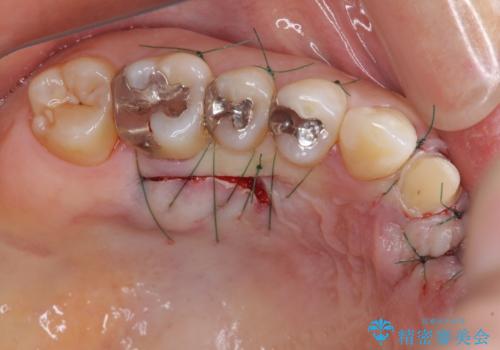

欠損部の歯肉が窪んでいるため、歯肉移植により形態を改善し、オールセラミックブリッジにて補綴することとしました。

- 外科手術のため、術後に痛みや腫れ、違和感を伴います

- 歯周組織再生治療は患者様の状態によって術後の経過が異なります(見た目が改善しない場合もあります)